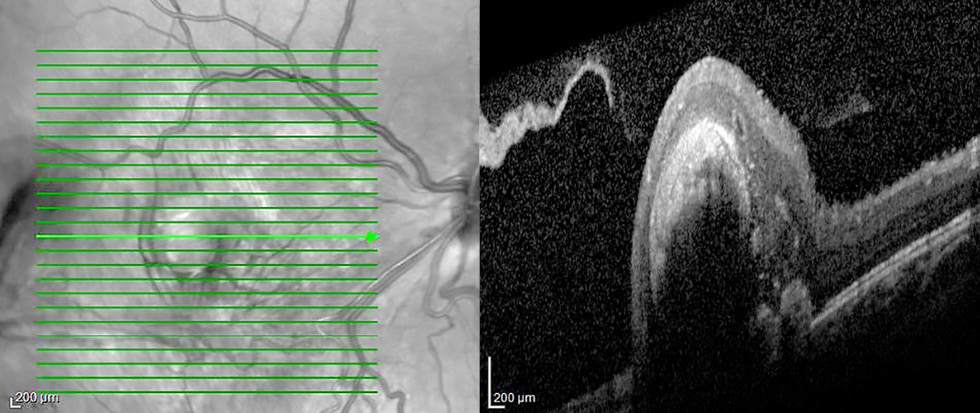

Рис 3. Оптическая когерентная томограмма комбинированной гамартомы сетчатки и ретинального пигментного эпителия: a — макулярная локализации у ребёнка 4 лет: деформация витреоретинального профиля макулярной зоны, утолщение и дезорганизация внутренних слоёв сетчатки, эпиретинальная мембрана. Максимально корригированная острота зрения 0,2; b — перипапиллярная локализация у ребёнка 4 лет: деформация витреоретинального профиля макулярной зоны, парапапиллярно с височной стороны утолщение и дезорганизация внутренних слоёв сетчатки, эпиретинальная мембрана. Максимально корригированная острота зрения 0,05.

Fig. 3. OCT of combined hamartoma of the retina and retinal pigment epithelium: a, macular localization in a 4-year-old child: deformation of the vitreoretinal profile in the macular zone, thickening and disorganization of inner retinal layers, epiretinal membrane. Best corrected visual acuity 0.2; b, peripapillary localization in a 4-year-old child: deformation of the vitreoretinal profile in the macular zone, parapaillary thickening and disorganization of inner retinal layers on the temporal side, epiretinal membrane. Best corrected visual acuity 0.05.

По данным ОКТ, максимальная толщина сетчатки в зоне гамартомы варьировала от 476 до 841 мкм (в среднем 691). ЭРМ определяли во всех случаях. Выраженный тракционный синдром, характеризующийся наличием складок сетчатки вследствие тангенциального натяжения, диагностирован у 10 детей [в 11 из 13 глаз с комбинированной гамартомой макулярной локализации (84,6%)] (рис. 2). В двух глазах с макулярной и перипапиллярной локализацией гамартомы отмечали незначительную тракцию сетчатки в центральной зоне со стороны ЭРМ (рис. 3).